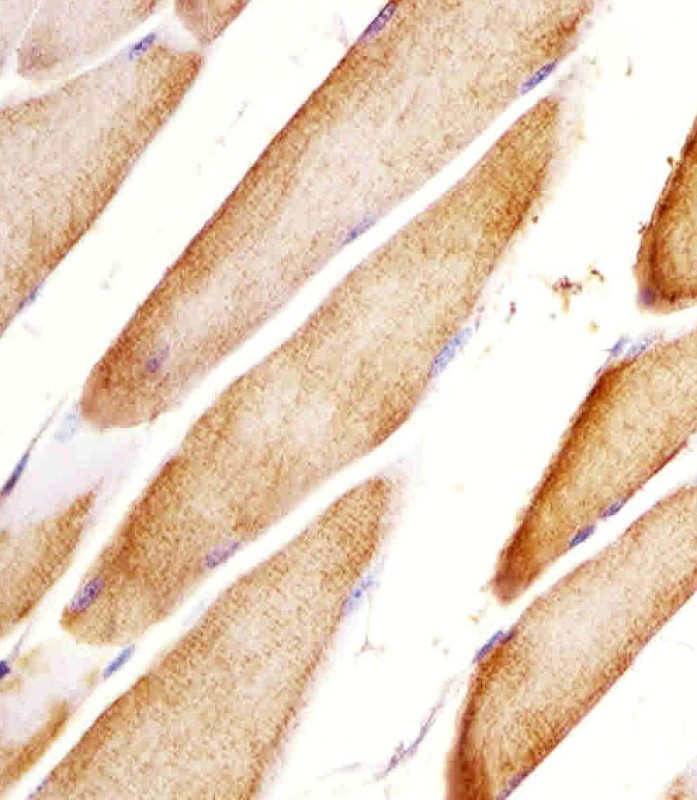

| IHC | 1/100-1/500 | Human,Mouse,Rat |

Widely used in techniques such as Western blotting, immunohistochemistry, and immunofluorescence, the Htr2a (N-term) antibody facilitates the study of receptor expression, localization, and trafficking in brain tissues, cell lines, or transfected systems. Its application extends to both basic research and drug discovery, particularly in exploring the mechanisms of psychedelics, antipsychotics, and antidepressants that modulate 5-HT2A activity. Validation via knockout controls or siRNA knockdown is recommended to confirm signal specificity. By enabling precise detection of 5-HT2A, this antibody supports advancements in understanding serotonin signaling and its therapeutic targeting.